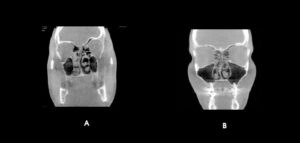

La reabsorción radicular interna (RRI) es una afección inflamatoria que resulta en la destrucción progresiva de la dentina intra-radicular a lo largo de los tercios